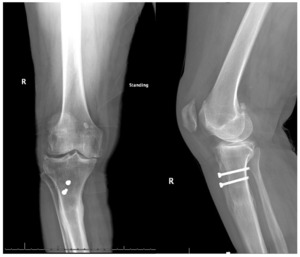

Pre-operative radiographs demonstrated Kellgren-Lawrence grade 4 tricompartmental osteoarthritis, 12° of tibial varus, a 22 mm deviation of the mechanical axis toward the medial side of the knee center, and an apex of angulation located 6 cm below the joint line (Figures 1 and 2). A follow-up computed tomography scan confirmed the absence of rotational malunion.

Physical examination disclosed active knee motion from 0° to 110°, a varus thrust during gait, and patellar subluxation near full extension. The collateral and cruciate ligaments were intact, and neurovascular integrity was preserved. Preoperative patient-reported outcomes included a Knee Society Score of 54 (pain 24, function 30) and a Knee Injury and Osteoarthritis Outcome Score for Joint Replacement (KOOS JR) of 49.